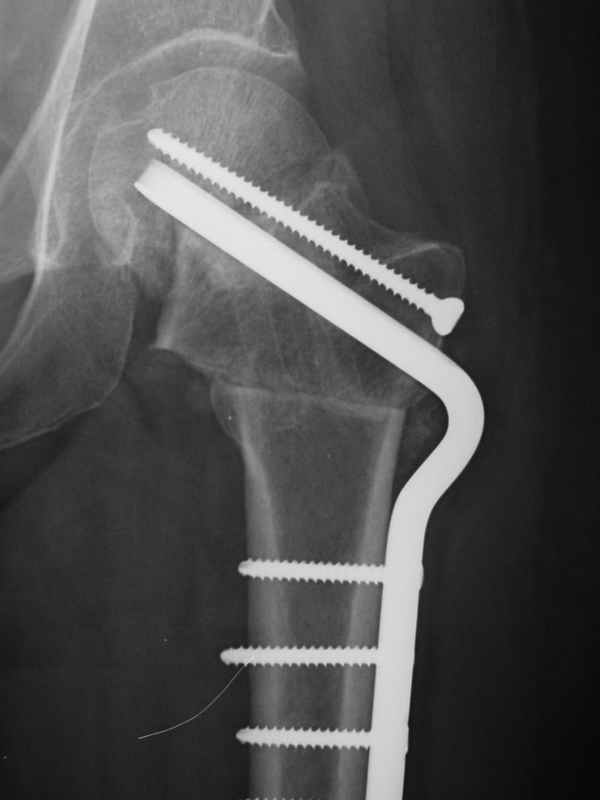

Re: Нелеченный перелом шейки бедра / Neglected fem

dhs will not correct improper biomechanical environment and may further compromise vascular

integrity consider establish vascular status via mri

and if viable follow with proximal valgus osteotomy

case provided s/p failed fixation